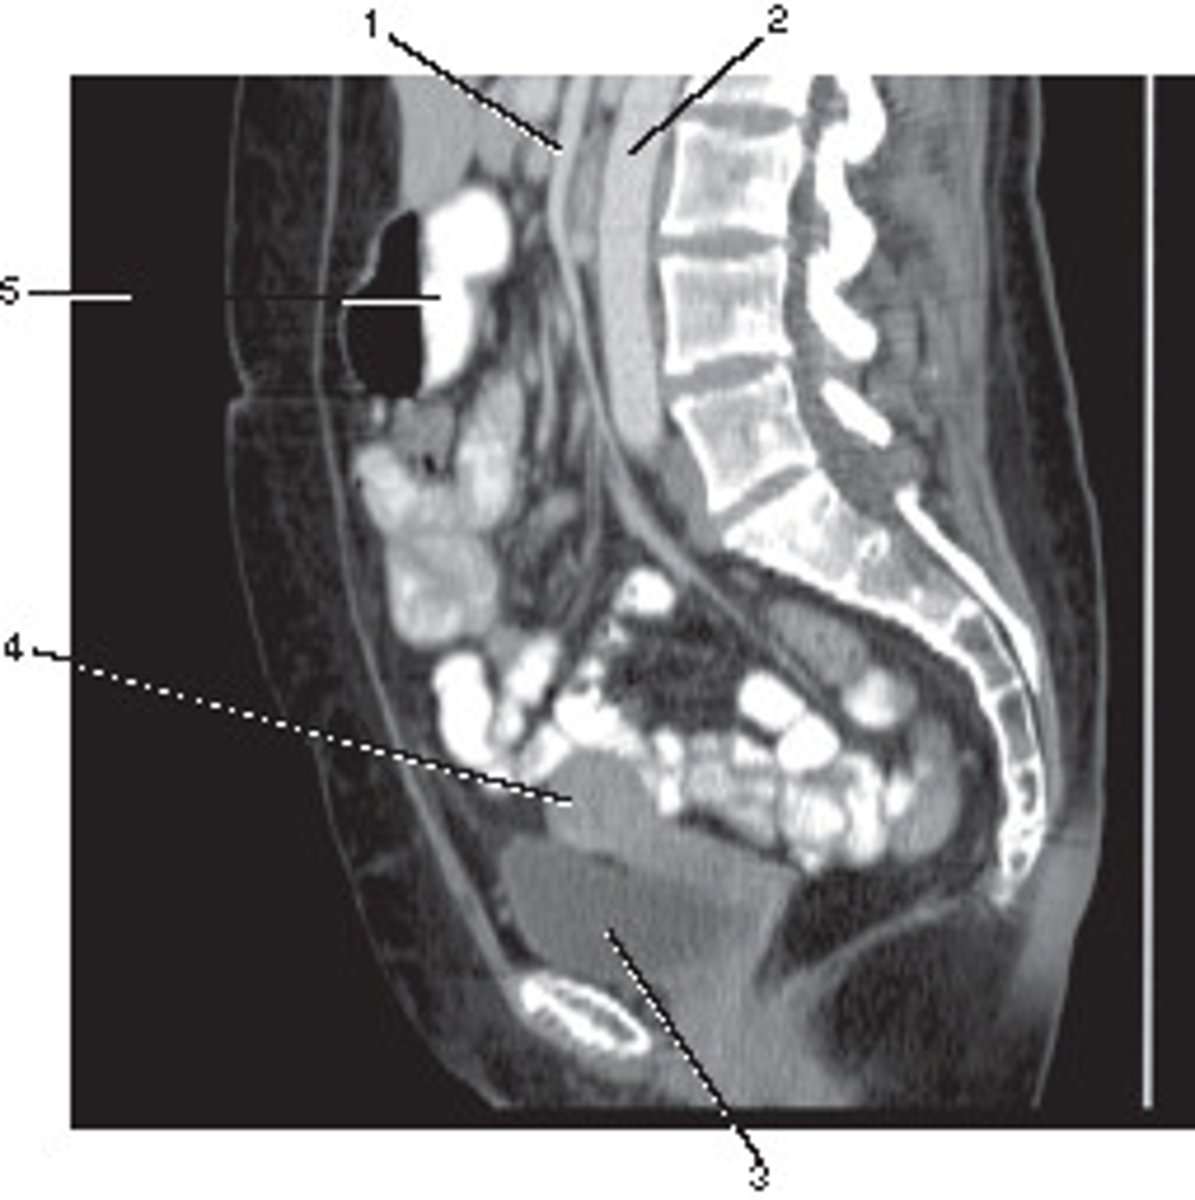

Sagittal

What anatomic plane best describes this image

<p>What anatomic plane best describes this image</p>

Corticomedullary;

30-40 seconds after injection,

the corticomedullary phase demonstrates optimal enhancement of the renal cortex with maximum differentiation from the renal medulla

This image of the abdomen was most likely acquired in which in which renal enhancement phase?

<p>This image of the abdomen was most likely acquired in which in which renal enhancement phase?</p>

Portal Vein

Number 1 corresponds to which of the following?

<p>Number 1 corresponds to which of the following?</p>

Superior Mesenteric Artery